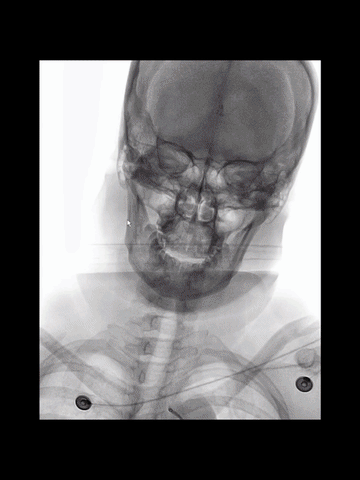

右股动脉穿刺置入8F短鞘,125cm长度5F多功能管塑成西蒙管头端形状,与6F长鞘(Cook,90cm)组成同轴,导丝导引下,5F管进入左锁骨下动脉,而后成其头端成西蒙管形,进入弓内。

西蒙管形头端超选入无名动脉,回拉导管时,习惯性进入右锁骨下动脉,间断冒烟下退回无名动脉,在旋转导管调整头端方向时,管头弹回弓内。

西蒙形管后续超选过程中,导管头还是习惯性进入左锁骨下动脉,调整导管头方向过程中,头端易弹回弓内。

耐心冒烟下,调整导管头在无名动脉内指向左侧,同时回拉导管,进入右CCA,后上高导丝,长鞘沿5F管顺利进入右CCA,后在导管导丝导引下,长鞘头端上高到右C1远端,建立可靠的治疗通路。